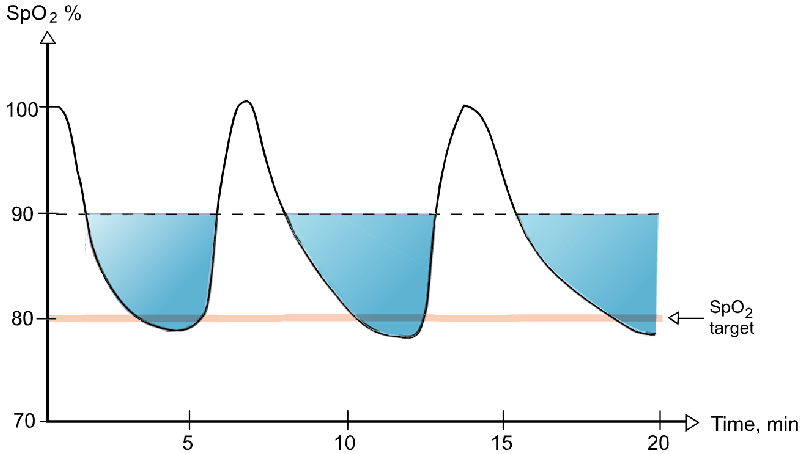

Hypoxemia – is a condition involving abnormally low blood oxygen levels. It can lead to bluish skin, difficulty breathing and fast heart rate. Apart from sleep apnea and higher altitudes, hypoxemia can be also be caused by many underlying illnesses, mainly lung and heart related especially in conditions of low environmental oxygen, diffusion impairment, hypoventilation, right -to left atrial shunting (image below).